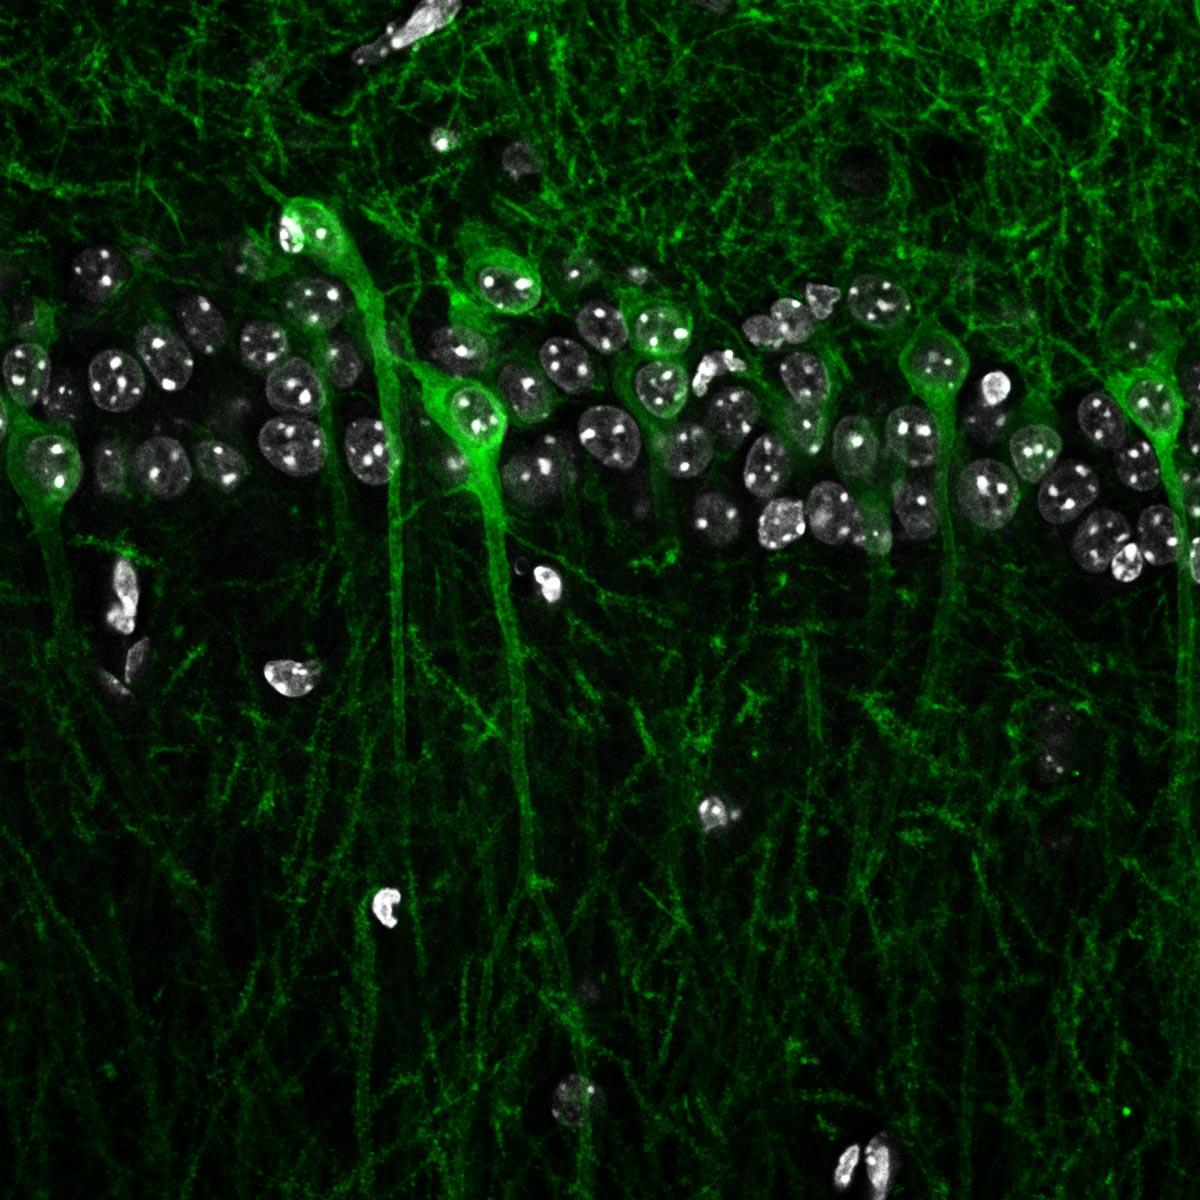

Home Video file Image News The MRC CoRE in Restorative Neural Dynamics has started! MRC Centre of Research Excellence in Restorative Neural Dynamics Logo for MRC Centre of Research Excellence in Restorative Neural Dynamics Home About Challenge News Research Outputs Papers Patents Preprints Datasets People Studentships MRC Centre of Research Excellence in Restorative Neural Dynamics Logo for MRC Centre of Research Excellence in Restorative Neural Dynamics Home About Challenge News Research Outputs Papers Patents Preprints Datasets People Studentships Home About Challenge News Research Outputs Papers Patents Preprints Datasets People Studentships MRC Centre of Research Excellence in Restorative Neural Dynamics Logo for MRC Centre of Research Excellence in Restorative Neural Dynamics Home About Challenge News Research Outputs Papers Patents Preprints Datasets People Studentships Harnessing neural dynamics to transform device-based therapy for brain conditions Learn more about our challenge. Explore our research. Latest news View all news Image 13 May 2026 Abhinav Sharma awarded CBR-UK DRI Fellowship Image 29 April 2026 MRC CoRE partners with NHS National Centre for Neurotechnology and Neurorestoration Image 27 April 2026 Ashwini Oswal awarded title of Associate Professor by the University of Oxford Vacancies Postdoctoral Neuroscientist- Preclinical Neurophysiology Application deadline: 29 May 2026 Postdoctoral Neuroscientist- Sleep-Related Neural Dynamics Application deadline: 29 May 2026 Project Manager Application deadline: 29 May 2026 Latest papers View all papers Dithering suppresses half-harmonic neural synchronisation to photic stimulation in humans. Suppression of pathological oscillations with transcranial focused ultrasound in Parkinson’s disease Thalamo-frontal functional connectivity patterns in Tourette Syndrome: Insights from combined intracranial DBS and EEG recordings. Decoding pre-movement neural activity from thalamic LFPs for adaptive neurostimulation in tremor patients Noradrenaline causes a spread of association in the hippocampal cognitive map